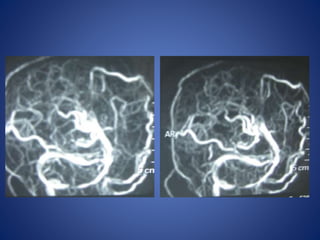

5 yrs male child with history of left sided focal seizures with secondary generalization

5 yrs malechild with history of left sided focal seizures with secondary generalization

Moya Moya

• Chronic progressive arteriopathy of unknown cause and has

become one of the most common causes of pediatric stroke.

• Suzuki and Kodama classified the evolution of moyamoya disease

using angiographic findings to define six phases of the disease:

Stage 1- Narrowing of carotid fork.

Stage 2- Initiation of basal moyamoya.

Stage 3- Intensification of moyamoya

Stage 4- Minimization of moyamoya.

Stage 5- Reduction of moyamoya .

Stage 6- Disappearance of moyamoya.

• Stenosis/occlusion of the distal ICA

• moyamoya vessels with signal voids in the basal ganglia

• ischemia

• infarction

• atrophy, and ventriculomegaly.

• Small abnormal net-like vessels proliferate giving "puff of smoke"

appearance.

• Contrast-enhanced T1WI - marked leptomeningeal enhancement

along the cortical sulci (ivy sign).

often show contrast stagnating in slow-flowing collateral

vessels both in the brain parenchymal and over its surface.

MR imaging